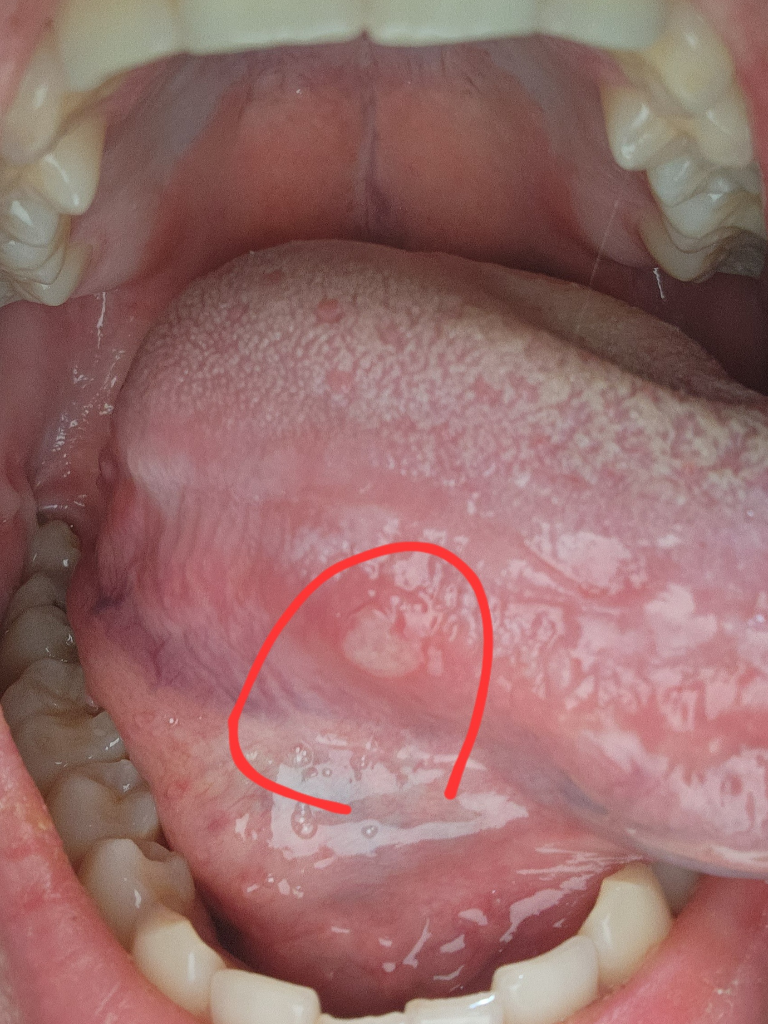

일주일 전에 첫번째 사진에보이는 혀옆부분에 큰 구내염이 났고요. 오늘 또 두번째사진에 보이는 혀 앞부분에 작은 구내염이났어요? 혀에 설염이 너무너무 자주생겨요 한달에 2.3번정도 생기는데 설암가능성있나요? 19살입니다.

• 1번 째 사진